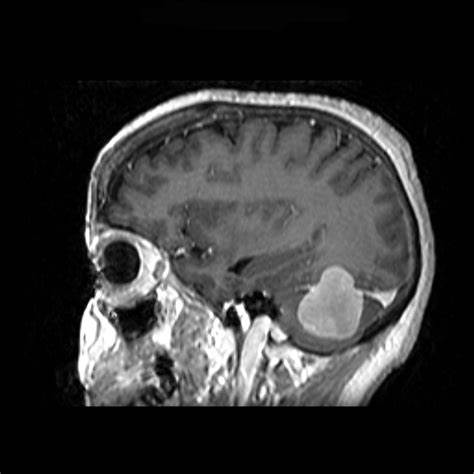

法国巴黎一位53岁男士,因三叉神经痛合并三叉神经感觉减退,在当地神经外科医院医院,查出左侧较大岩斜脑膜瘤(27立方厘米)。脑磁共振(mri)显示从幕部可见明显的轴外肿瘤,岩斜向外扩张,对脑干有明显的挤压效应。经该院神经外科教授兼主席Sebastien Froelich教授主刀手术后,这个复杂位置的脑膜瘤得以完整切除,无神经功能损伤及相关的并发症。

从以上患者术前的影像中可以看出,肿瘤位置距离头皮远,术中需要穿过很深的正常脑组织以及相应血管,所以手术入路不清晰,很多情况下往往只切除一点。加上手术难度较大,很可能发生切除率较低,甚至可能发生术中出血而提前终止手术的情况。即使手术做了,也可能造成偏瘫等严重的不可逆的神经损伤,使患者终身遭受手术后遗症的困扰。岩斜区脑瘤的死亡率和致残率如此之高,选择适当的个体化治疗方案至关重要。” Sebastien Froelich教授指出。‘

图示:通过这例手术对比术前术后影像对比,可见术后切除率达到了近乎全切。而患者术后并没有明显得神经损伤症状。